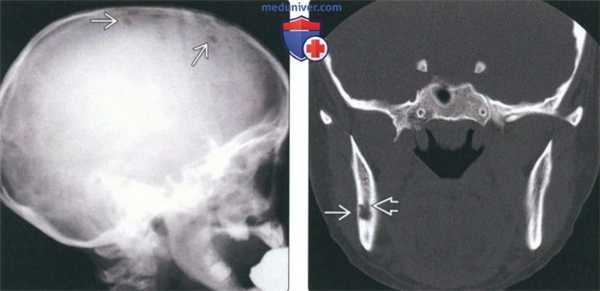

(Слева) На аксиальной КТ в костном окне у этой же пациентки визуализируется очаг в ветви и отдельно лежащий очаг спереди от него, хуже отграниченный и с более выраженной деструкцией. Между очагами визуализируется нижнечелюстной канал.

(Справа) На корональной КТ в костном окне у этой же пациентки определяется деструкция язычной кортикальной пластинки, обусловленная очагом большего размера. Обратите внимание на нижнечелюстной канал внизу. В этом случае имеет место моно-стотическая эозинофильная гранулема с изолированным поражением ветви справа: прогноз благоприятный.

3. КТ при лангергансоклеточном гистиоцитозе челюсти:

• КТ в костном окне и КЛКТ:

о Оценка размеров остеолитических очагов в верхней и нижней челюсти

о На КЛКТ также могут обнаруживаться поражения черепа (в зависимости от поля зрения)

о Позволяют лучше идентифицировать периостальную реакцию